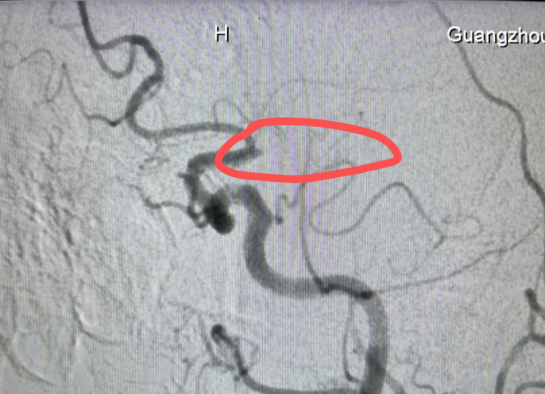

术中,通过取栓支架取出两块血栓,复查造影可见左侧大脑中动脉M1段再通,左侧大脑中动脉M1段重度狭窄,狭窄率约70%,于是继续经导管注入药物,直到显示左侧大脑中动脉M1段狭窄率恢复至60%。

(经介入取栓治疗后,左侧大脑中动脉再通,血流恢复良好)